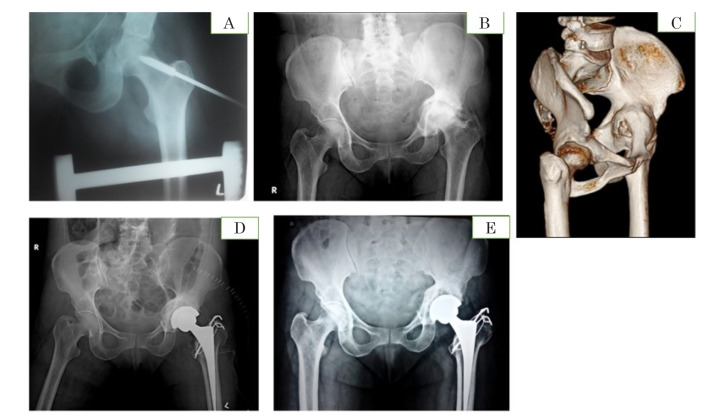

Materials and methods: This longitudinal comparative study, which included 40 patients who underwent THR for either posttraumatic arthritis after fixation of an acetabular fracture or arthritis following conservative management of a fracture, was conducted for 60 months. Twenty-four patients had undergone ORIF, and 16 patients had undergone nonoperative/conservative management for acetabular fractures. Following THR, the patients were followed up for monitoring of functional outcomes for the Harris hip score (HHS) and comparison between the ORIF and non-ORIF groups was performed.

Results: The HHS showed significant improvement in both ORIF and non-ORIF groups. At the end of the mean follow-up period, no significant variation in scores was observed between the groups, i.e., ORIF group (91.61±6.64) compared to non-ORIF group (85.74±11.56). A significantly higher number of re-interventions were required for medial wall fractures and combined fractures compared to posterior fractures (P<0.05).

Conclusion: THR resulted in improved functional outcome during follow-up in both the groups; however, the ORIF group was observed to have better functional outcome. Re-intervention was not required for any of the posterior fractures at the end of the mean follow-up period.